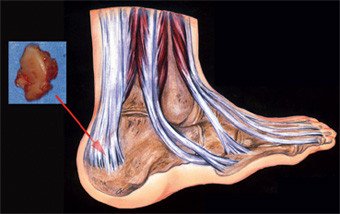

Verklebungen der Sehne zum Fersenbein sind mitverantwortlich für lange, unbefriedigende postoperative Verläufe. Seit über 10 Jahren verwenden wir deshalb an der Schulthess Klinik eine andere Operationstechnik für die Behandlung der Haglund-Ferse. Das Prinzip dieser Operation ist eine «indirekte» Entfernung des Überbeins, die den störenden Knochen von der Achillessehne wegklappt. Das Überbein verschwindet, die Gleitschicht bleibt aber erhalten. Die Sehne und die chronische Schleimbeutelentzündung können sich erholen.

Durch die «indirekte» Resektion wird die empfindliche Stelle an der Ferse mit ihrer Gleitschicht gar nicht berührt und bleibt intakt. Dieses Operationsverfahren wurde bereits vor vielen Jahren erstmals beschrieben, gelangte jedoch zunehmend in Vergessenheit. Wir entdeckten das Verfahren sozusagen neu und wendeten es zunächst nur bei der klassischen Haglund-Ferse an, die keine sichtbaren Veränderungen an der Achillessehne zeigt. Ermutigt durch die guten Erfolge begannen wir das Operationsverfahren auch bei Fällen mit begleitender Sehnendegeneration anzuwenden. Die Operation wird in einer auf den Fuss beschränkten Narkose durchgeführt.